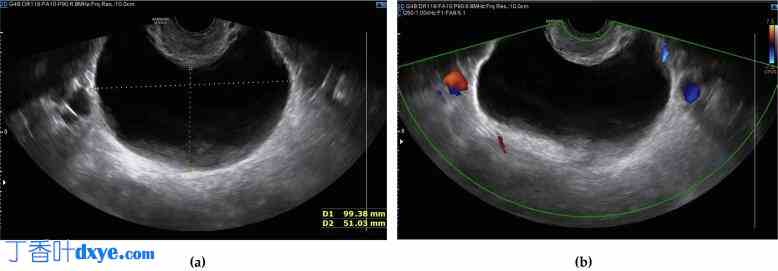

入院后,经阴道盆腔超声检查证实了诊断,显示左侧髂窝内有一个 99x51 毫米的肿块,提示卵巢起源。超声显示内部和外部边缘清晰,无回声,颜色评分为 1,表明良性特征符合 IOTA 术语的 B1 简单规则(图 1)(Timmerman 等人,2008 年 Jun,Timmerman 等人,2016 年 4 月,Valentin 等人,2013 年 1 月,Nunes 等人,2014 年 11 月,Suryawanshi 等人, 2024 年 8 月 21 日,Vilendecic 等人,2023)。子宫增大,外观不均匀,提示子宫纤维瘤病,而右侧卵巢看起来正常。肿瘤标志物,包括 CA125、CA 19.9 和 CEA,均为阴性。

图 1.

(a) 盆腔超声扫描显示左髂窝内有一个 99×51 mm 的肿块,疑似卵巢来源,其特征为内外边界清晰,内部无回声。超声设备:三星 WS80A。(b) 盆腔超声扫描显示该肿块,彩色多普勒未见血流信号。超声设备:三星 WS80A。